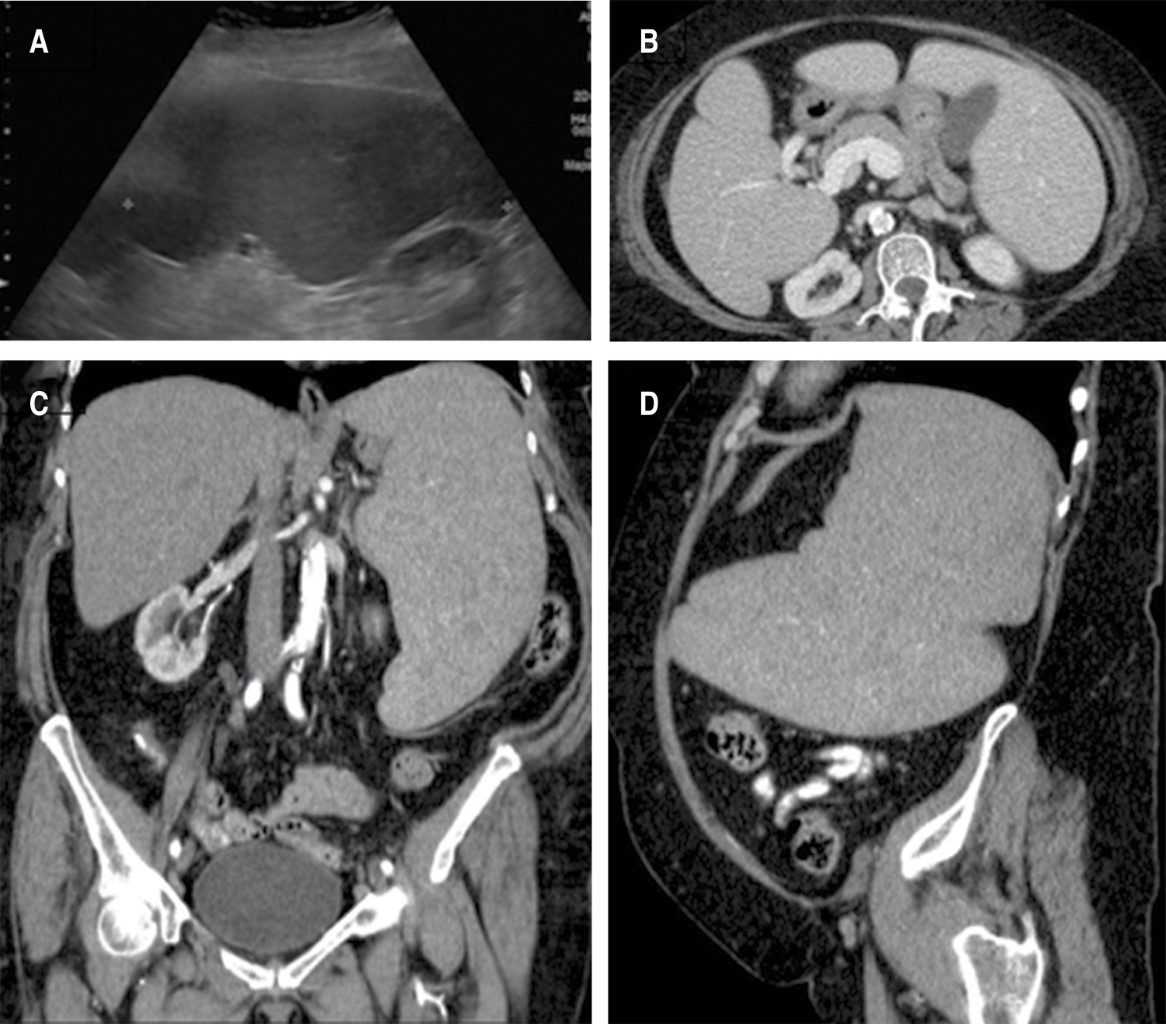

Introduction: Minimally invasive surgery has constantly evolved since the 1980's; multiple international centres have developed devices and approaches with the intention of reducing the risk of haemorrhage, postoperative pain and hospital stay, as well as improving cosmetic results. These improvements have positioned laparoscopic approach as the main option for the non – urgent splenic resection. Methods and material: The case presents a 74-year-old female with multiple comorbidities, chronic anemia and difuse abdominal pain, predominant in the upper left cuadrant; palpable splenomegaly down to the left iliac crest; US and CT shows a 20 × 17 × 8 cm spleen, with a calculated volume of 1400 cm3. Hand-assisted laparoscopic approach is performed through 3 ports; vascular control with endostapler, finding a 25 × 15 × 10 cm spleen. Results: Satisfactory postoperative evolution and patient discharge at day 4 with significant haemoglobin rise and cese of abdominal pain. Conclusion: Integral selection and meeting of criteria in patients with massive splenomegalia, improves the surgical treatment. Hand-assisted laparoscopic splenectomy (HALS) is a viable option, which allows an optimized movility of the spleen and adjacent structures and which reduce the risk of surgical convertion to open surgery, less associated morbility and still preserves the benefits of minimally invasive surgery.

Figure 1